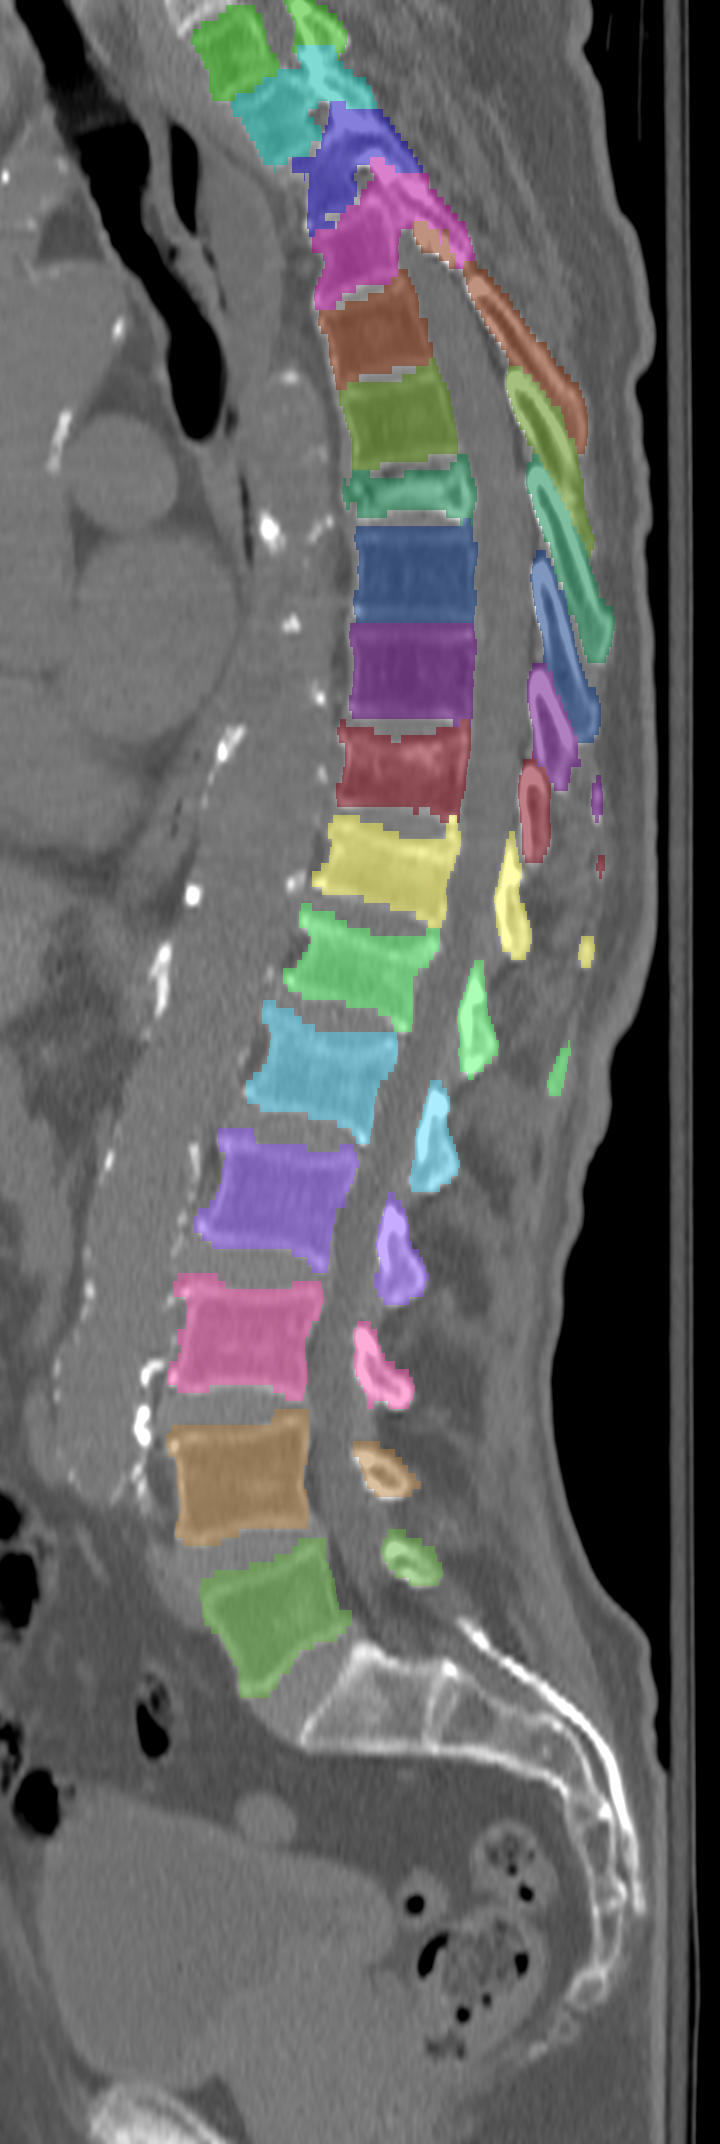

Normalized CT images and reference segmentations of thoracic and lumbar vertebrae from the CSI 2014 workshop

Description

This is the dataset of the vertebra segmentation challenge of the CSI 2014 workshop that was held in conjunction with MICCAI 2014.

- Vertebrae have been anatomically labeled (8 = T1, 9 = T2, ..., 24 = L5)

The resolution and segmentation quality of the diseased cases (16-20) is quite low.